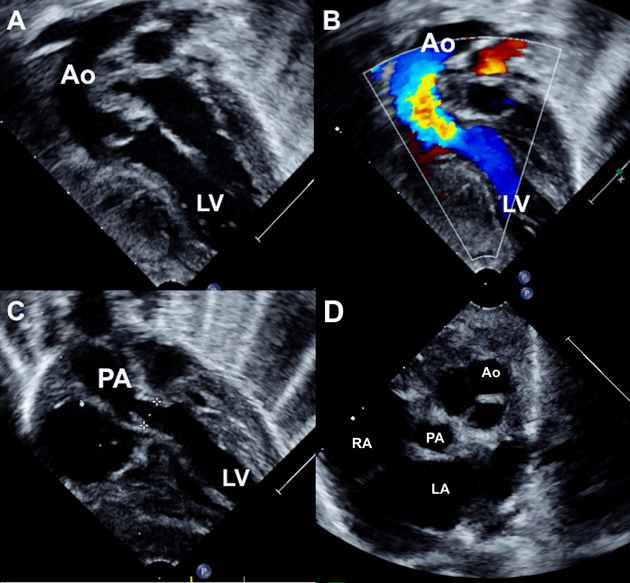

Fig. 1 Echocardiogram of first patient (Movie 1)

Subxiphoid coronal view (A) shows origin of both aorta and pulmonary artery from the left ventricle. Parasternal long axis rightward sweep (B) demonstrates aortomitral fibrous continuity with large subaortic VSD associated with aortic override of 50%. On a leftward sweep (C), pulmonary mitral fibrous continuity is seen while the VSD disappears in this view. Color flow imaging in the corresponding same three images (D, E, F) confirm the blood flows from the left ventricle to both great arteries; the mild flow turbulence in pulmonary annulus is caused by large pulmonary flows. Ao, aorta; LA, left atrium LV, left ventricle PA, pulmonary artery; RA, right atrium; RV, right ventricle.